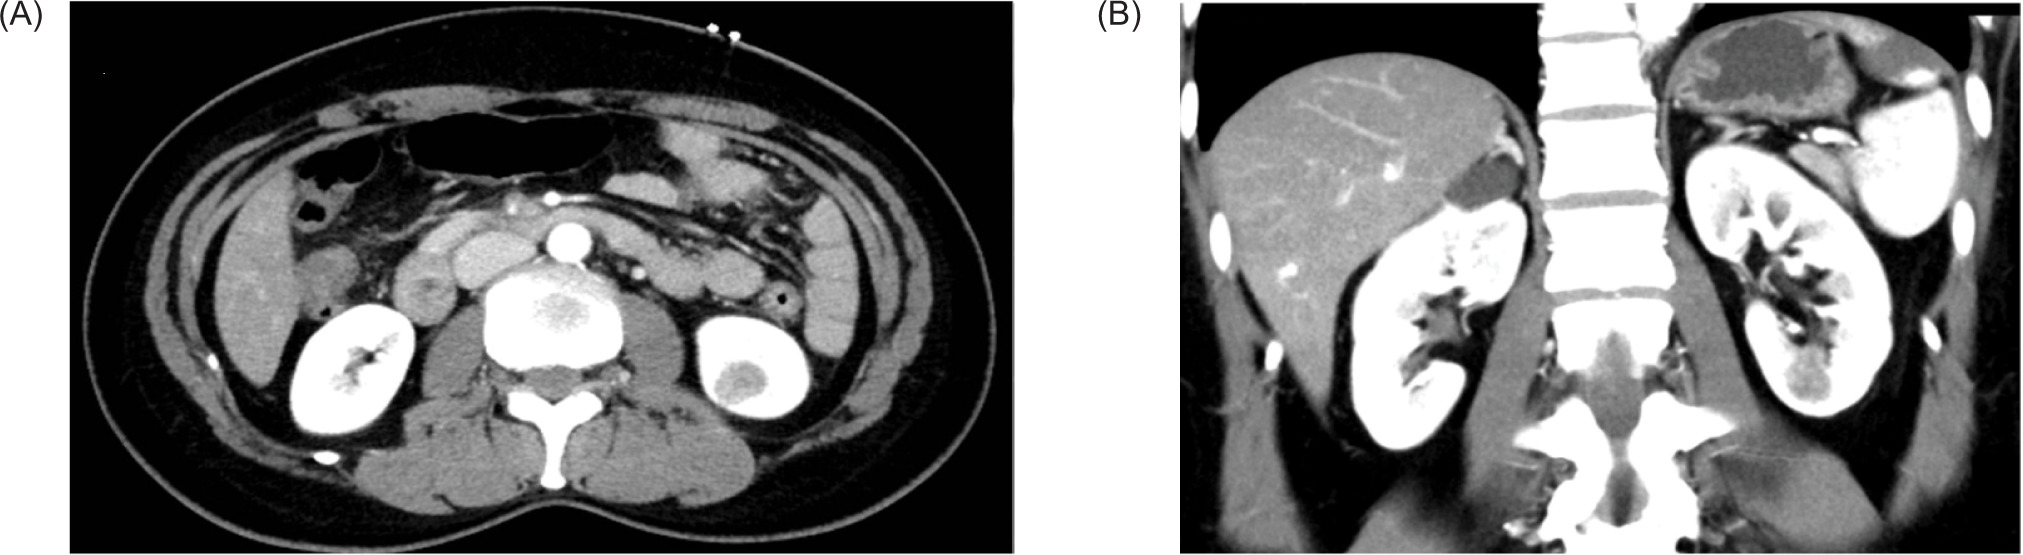

A 51-year-old lady presented to our institute with abdominal pain. Physical examination was unremarkable. Ultrasound of the abdomen showed a 1.6 cm hyperechoic mass at the lower pole of the left kidney. A computed tomography (CT) scan was thus performed, which showed a 1.7 × 1.4 × 1.7 cm hypodense contrast-enhanced lesion in the lower pole of the left kidney (Figure 1); the mass was mainly endophytic. There was no invasion to the perinephric fat and the renal vein was patent. The RENAL nephrometry score was 7. A robotic-assisted laparoscopic left partial nephrectomy was performed with the left lower pole branch selective clamping. The total warm ischemic time was 25 minutes. There was no complication.

Figure 1: Contrast-enhanced computed tomography images. (A) axial image, (B) coronal image.